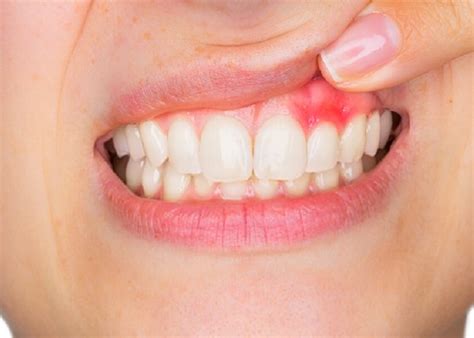

In the earliest stage, gingivitis may be barely noticeable. You might observe slight redness along the gum line, particularly between teeth where plaque tends to accumulate. The gums may feel slightly tender when touched, and you might notice occasional light bleeding when brushing vigorously. At this stage, the changes are subtle, and many people dismiss them as normal or temporary irritation.

As gingivitis progresses to a moderate stage, the symptoms become more pronounced. The redness spreads from the gum line to cover more of the gum tissue, and swelling becomes more obvious. Bleeding occurs more frequently and with less provocation—you might see blood in the sink after normal brushing. The gums may start to pull away from the teeth slightly, creating small pockets where bacteria can accumulate. Bad breath becomes more persistent and noticeable.

Between teeth (interdental areas) Difficult to clean, plaque accumulates easily Red, swollen triangular tissue between teeth, bleeding when flossing